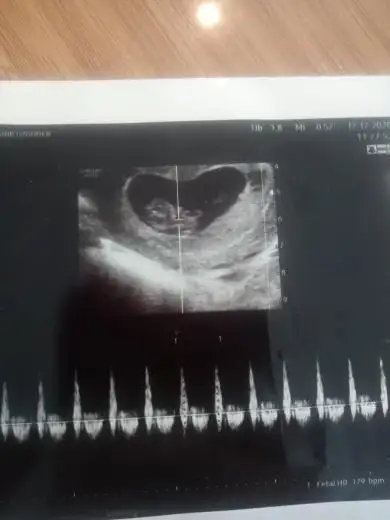

Kiz sankiEki Görüntüle 2777702 Eki Görüntüle 2777703 Eki Görüntüle 2777704 6+4 7+4 11+4 yorumlayabilir misiniz? Henüz belli olmadı cinsiyetimiz

Erkek gibiBenim bebişimide yorumlar mısın vajinal bu arada 6+2 haftalık Eki Görüntüle 2779354 Eki Görüntüle 2779356

Bu arada üstten ultrasondur. 8 haftalık ben plasentayi sağda gördüm. Yanlış görmedim isem tabi ama yorumlayamadim... Yorumlarınızı bekliyorum...Benim bebeğim de 8 haftalık burada plasenta sağda gibi geldi. Ama yorumlayamadim.. yorumlarınızı bekliyorum ramzi teorisi ile